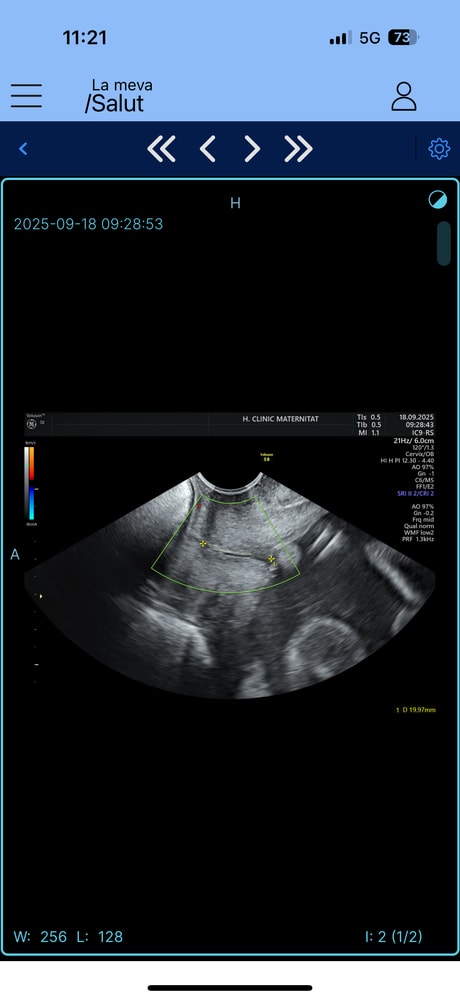

Blanche, вот они почему-то замеряют только часть чёрной линии. Не знпю почему Изображение

Blanche, прогестерон я принимаю, это обязательно. Но получается это очень тонкая грань кто как меряет эту шейку, у меня замеры фактически три дня подряд у разных врачей : 30 мм-26 мм-22мм минимальные